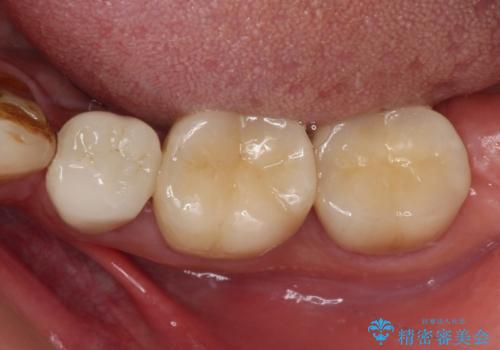

虫歯を取り除き、仮歯を装着した時点でしみる感覚は改善されました。

オールセラミッククラウン装着後も経過は良好です。